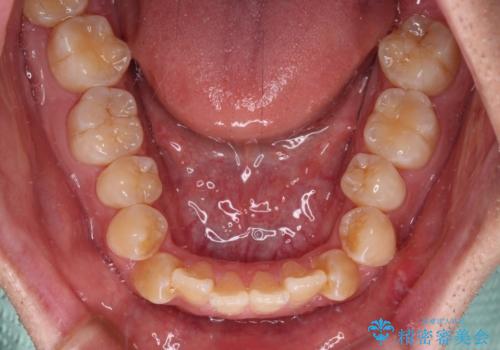

オープンバイトは舌の突出癖により誘発され、治療後も突出癖が残っている容易に後戻りしてしまいます。

治療期間を短縮するためにも、舌突出癖の改善が極めて重要となります。

特にインビザラインではIPRという歯と歯の間を削る処置を多用するため、後戻りによりスペースが生じやすくなるため、治療初期段階での舌のトレーニングが必須となります。